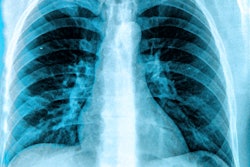

For their experiment, the researchers used geometry that was consistent with an imaging protocol for thoracic and abdominal interventional procedures. The setup also allowed the group to isolate the radiation dose emitting from the phantom, rather than directly from the x-ray tube.

Ashley Tao, PhD, a medical physics resident, and colleagues looked at the scatter from three different manufacturers' x-ray tubes. The systems were configured to produce similar beams and an equivalent magnitude of scatter originating from within the phantom for all systems.

The analysis revealed that x-ray scatter coming from the x-ray collimator contributed substantially to the radiation dose measured at the hypothetical location of the interventional physician's upper torso. The researchers also observed a minimum of 20% tube scatter at all distances from the central axis of the x-ray beam.

"Considering all x-ray tubes and variable distance from the central x-ray, scatter emitting from the beam exit window of the tubes accounted for 20% to 55% of the total scatter," they noted.